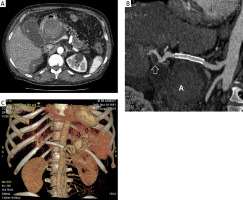

Figure 1

A – Computed tomography (CT) image of the abdominal arterial phase (acquisition about 20 s after intravenous administration of a contrast agent at the level of the epigastrium) – a small aneurysm with a parietal thrombus located in the distal part of the hepatic artery is visible (black arrow). Superficially located distended gallbladder (G). Lateral to the midline, a large aneurysm with an irregular parietal thrombus located along the course of the splenic artery (white arrow) is visible. B – CT image of the abdominal arterial phase (acquisition about 20 s after intravenous injection of a contrast agent at the level of the epigastrium 6 cm below) showing a large aneurysm, 80 mm in diameter, with irregular parietal thrombus and obliterated external contours, located along the course of the common hepatic artery (white arrow). Lateral visible gallbladder (G). Surrounding the liver, fluid is visible (B). C – CT image of the arterial phase – 3D reconstruction shows a prominent small aneurysm with parietal thrombus located in the distal part of the hepatic artery (white arrow). A large ruptured aneurysm along the course of the common hepatic artery (red arrow). Along the course of the tortuous splenic artery, 3 aneurysms are located (black arrows)